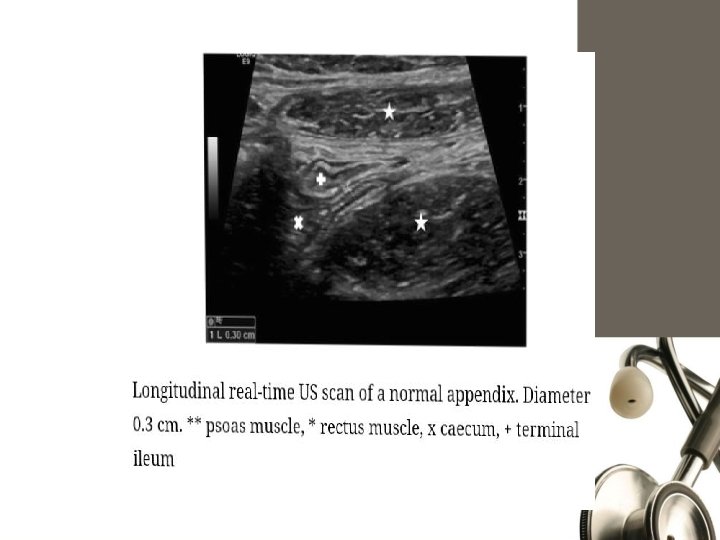

Graded Compression U/S Blind ending nonperistaltic bowel loop. Non compressible. Thickened wall>3 mm, lumen >6 mm. Presence of periappendicular fluid. Target sign. Appendicolith.